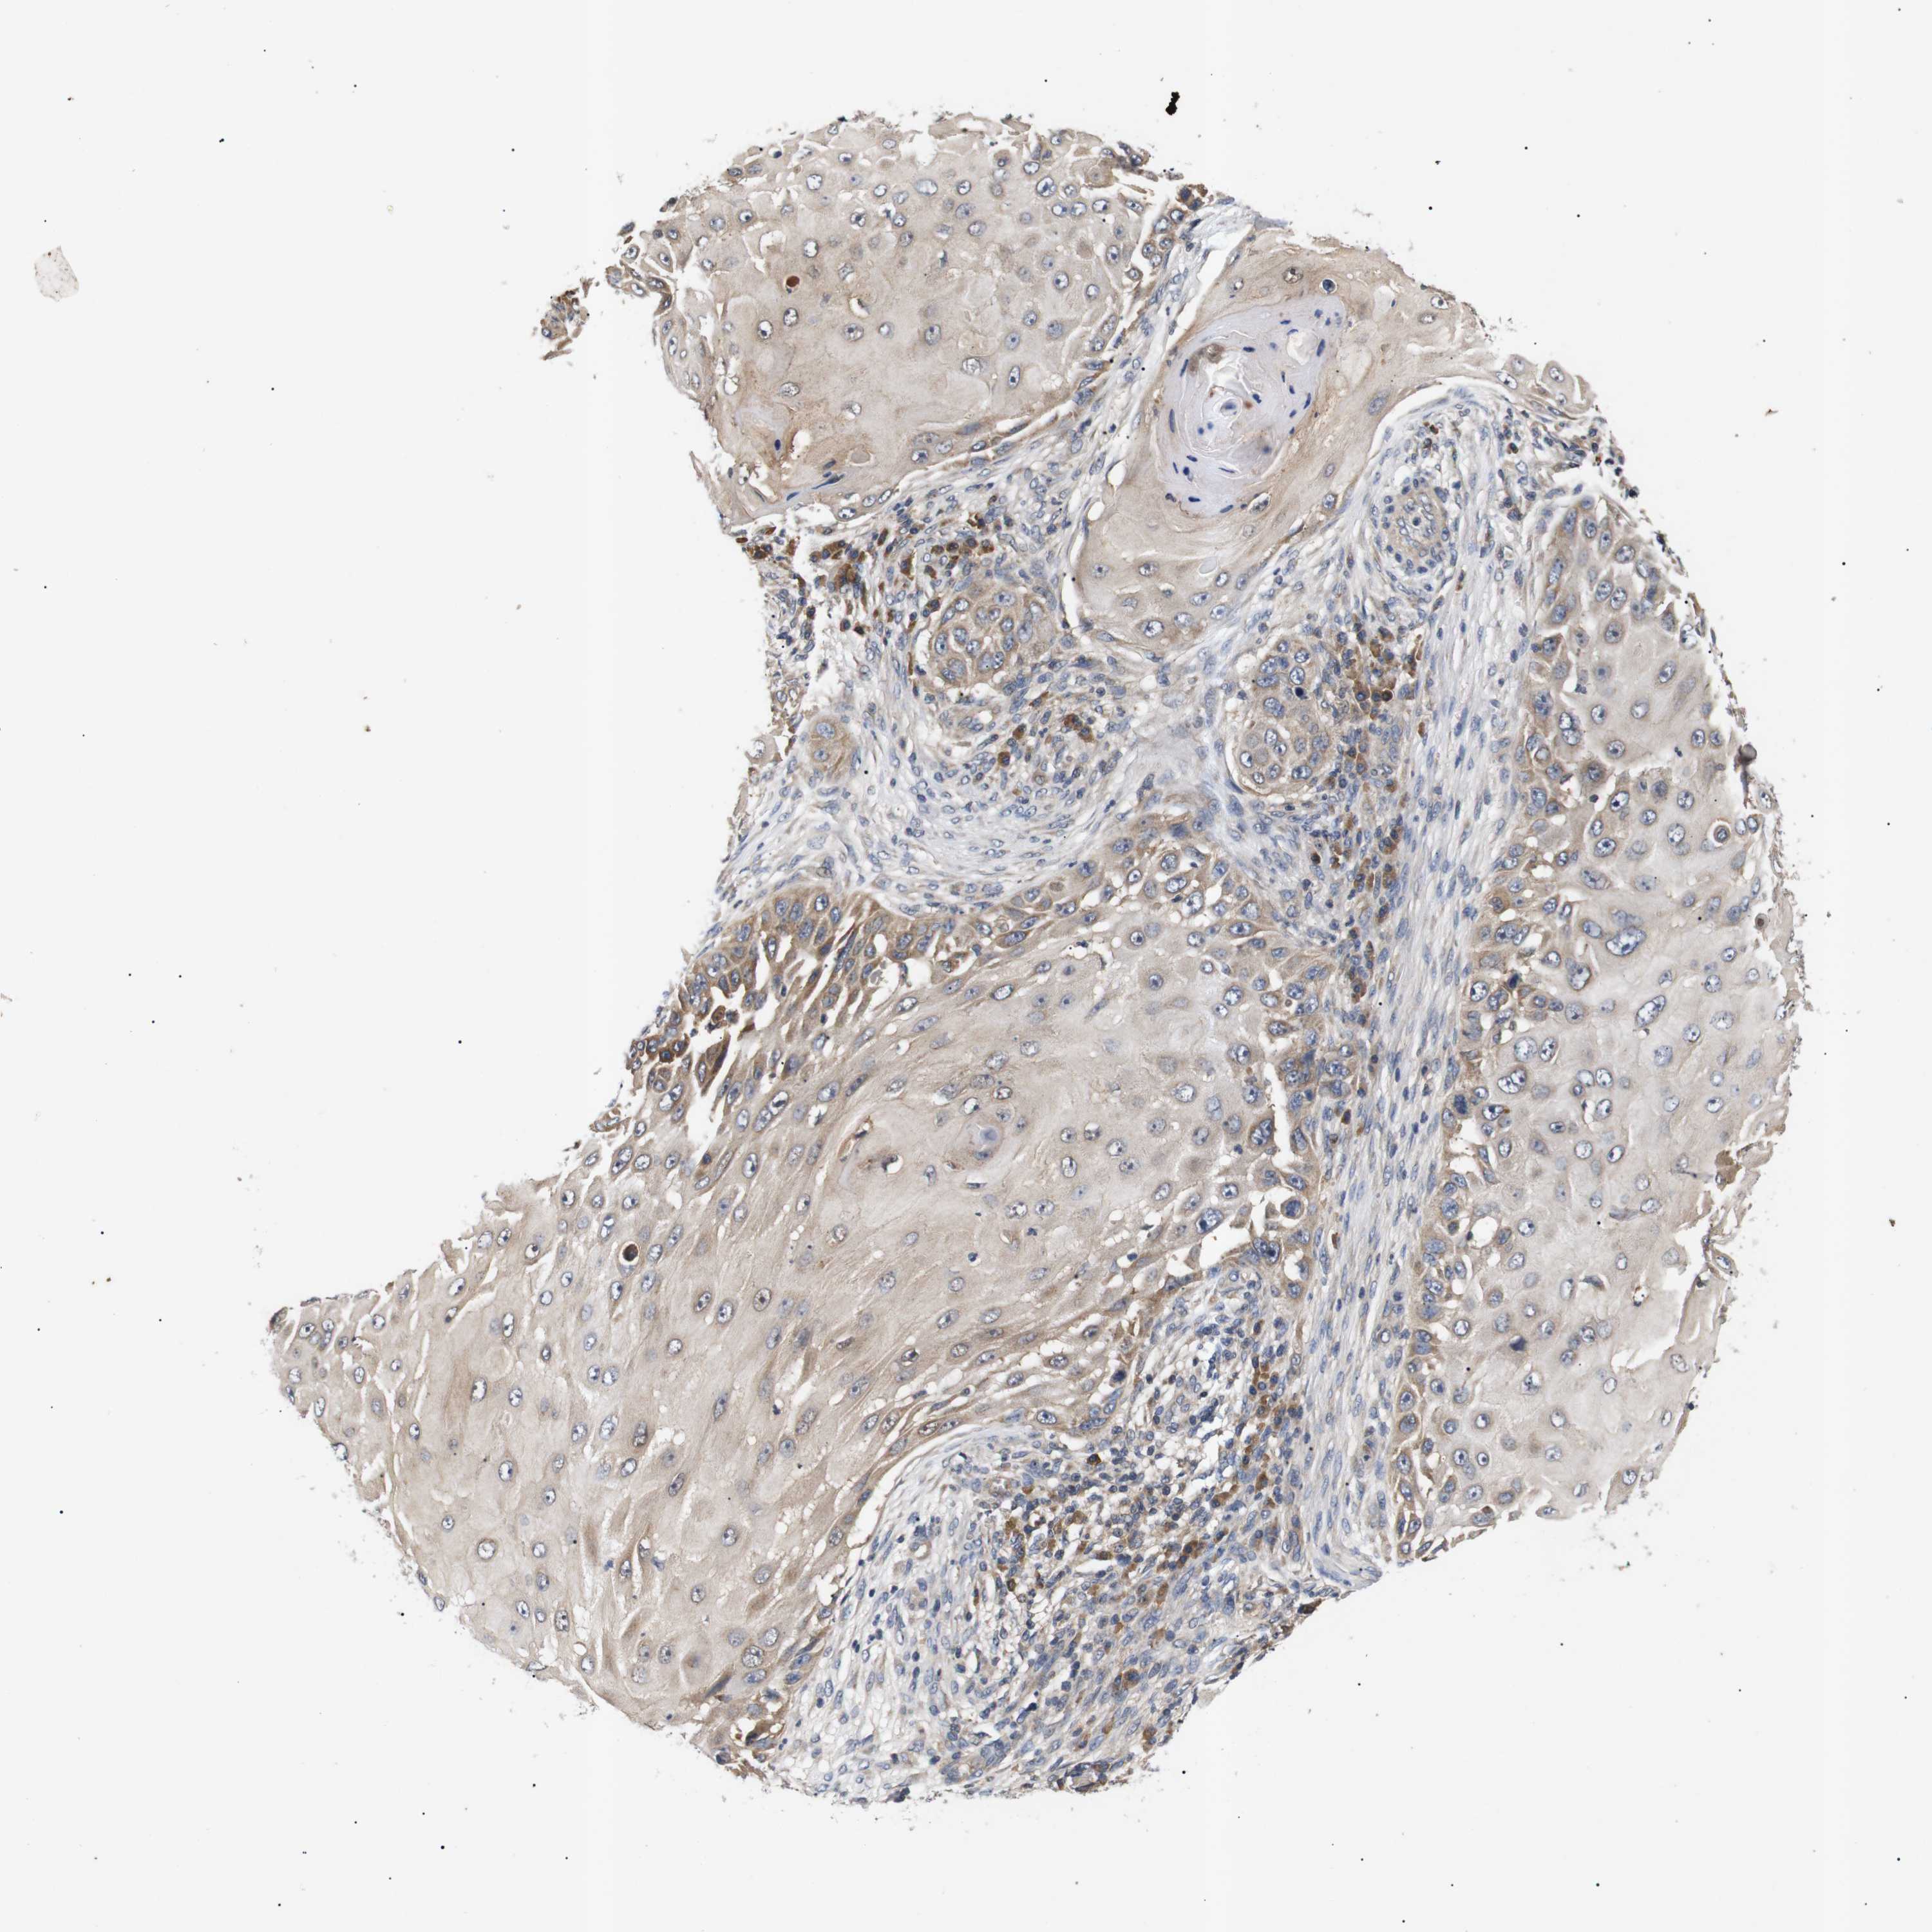

SKIN CANCER - Protein expressioni

A mouse-over function shows sample information and annotation data. Click on an image to view it in a full screen mode. Samples can be filtered based on level of antibody staining by selecting one or several of the following categories: high, medium, low and not detected. The assay and annotation is described here.

Each image is clickable and will lead to virtual microscopy that enables deeper exploration of all samples and also displays staining intensity scores, fraction scores and subcellular localization as well as patient and tissue information for each sample.

Antibody HPA015257

Medium

Moderate

75%-25%

Location

Cytoplasmic/membranous

Basal cell carcinoma

Adnexal tumor, benign